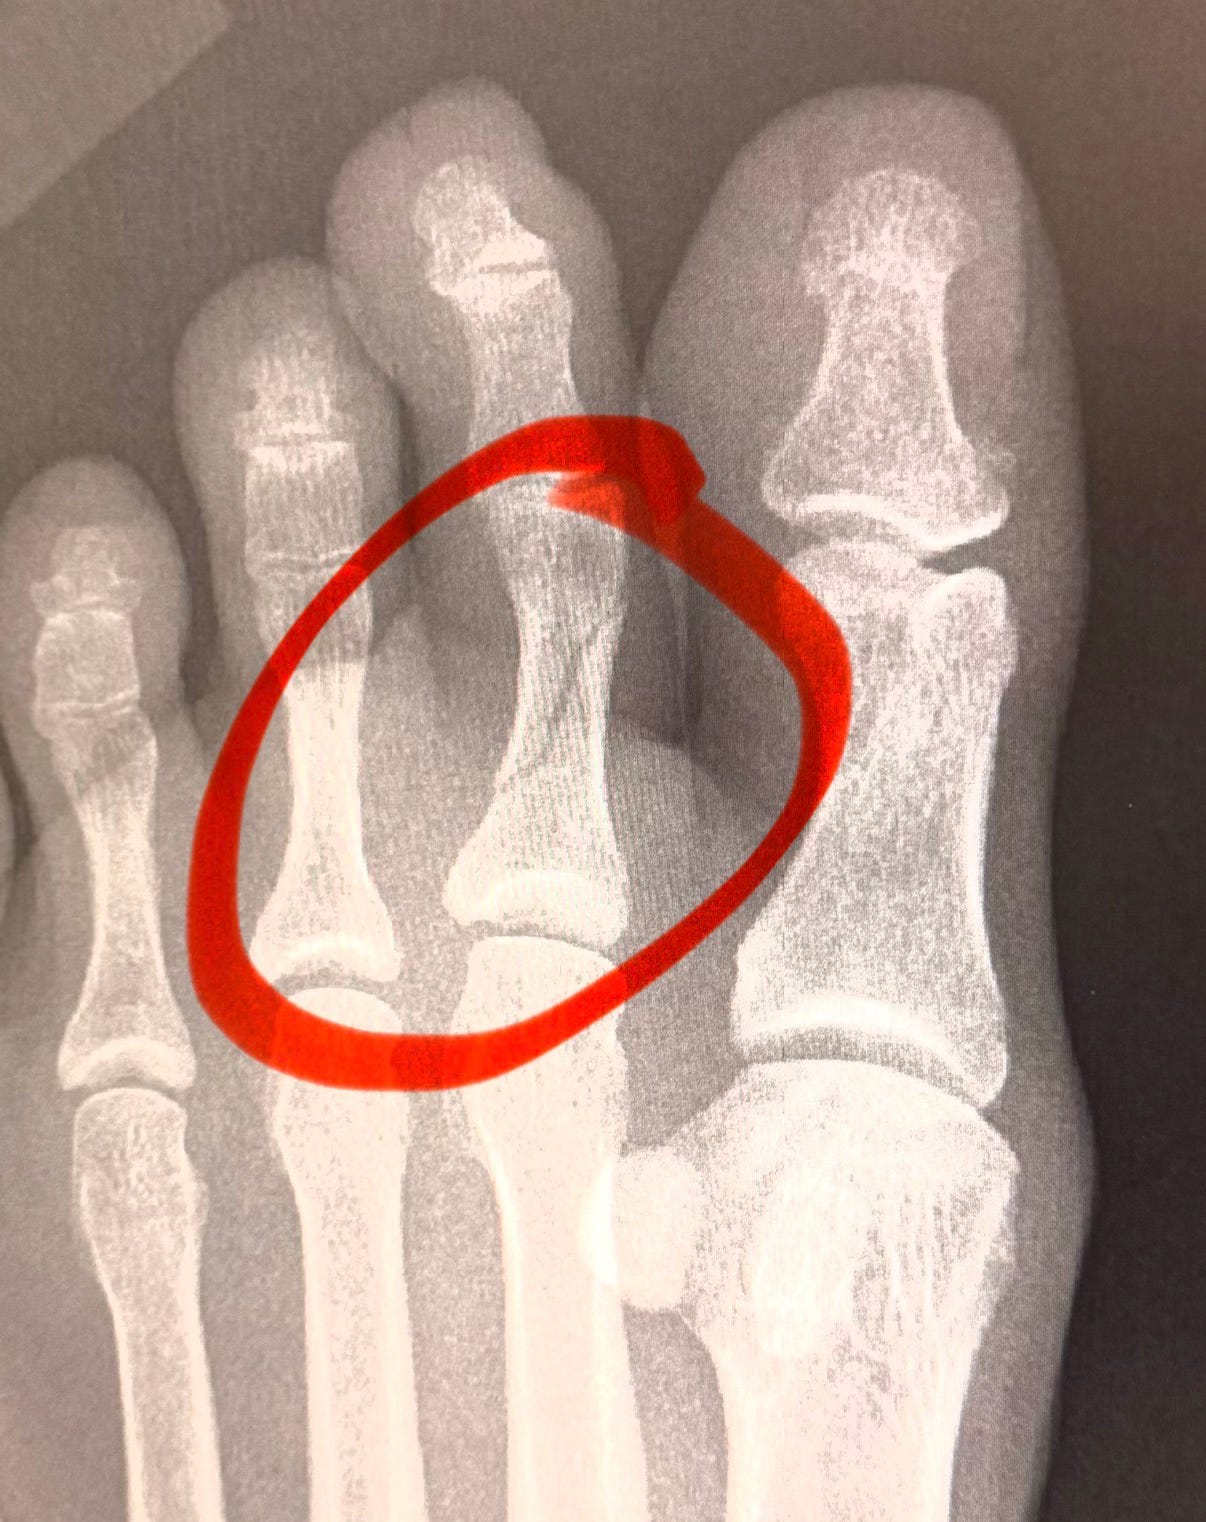

Turns out I cleanly broke that little buddy diagonally across.

My first broken bone, too.